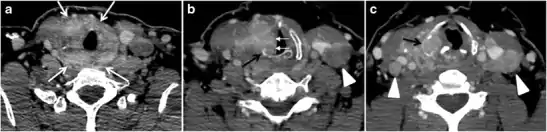

Fig. 6. A 61-year-old female patient with locally aggressive PTC. an Enhanced axial CT scan of the neck demonstrates a heterogeneous infiltrative thyroid mass. This mass diffusely involves the entire gland and circumferentially encases the trachea with involvement of bilateral tracheoesophageal grooves (white arrows). b, c Additional axial cranial images show right cricoid cartilage destruction (black arrows in b), right thyroid cartilage destruction (black arrow in c), right vocal cord paralysis (white arrows in b), and bilateral cervical lymphadenopathy (arrowheads).[1]

Fig. 11. Thyroid non-Hodgkin's large B-cell lymphoma in a 66-year-old female patient. an Axial enhanced neck CT scan demonstrates left thyroid lobe and isthmus homogeneously hypodense and minimally enhancing mass (white arrows). This lesion invades the prevertebral muscles (black arrows). Note the multiple enlarged level V lymph nodes (white arrowheads). b Post-treatment image shows significant reduction in size and mass effect of the left thyroid infiltrative mass, with almost complete resolution of the left cervical lymphadenopathy.[1]

Fig. 12. Diffuse thyroid large B-cell lymphoma in a 79-year-old female patient. an Axial enhanced neck CT scan demonstrates a homogeneously hypodense and minimally enhancing large right thyroid solid mass (long white arrow) extending into the thyroid isthmus. It is encasing the right carotid artery (short white arrow) and displacing of the trachea and oesophagus to the left side.[1]